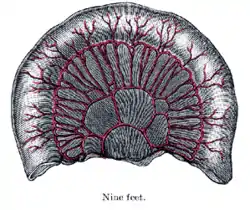

Toward the ileocolic junction, secondary and tertiary loops are observed, the vessels are smaller and become obscured by numerous fat-tabs.

The diagrams below show the arrangement and variations of the loops of the mesenteric vessels for various segments of the small intestine of average length: